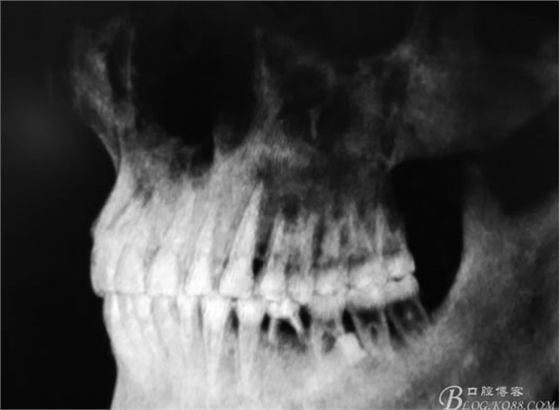

外科程序: